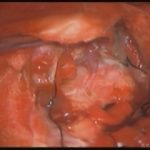

手術前1

摘出 前